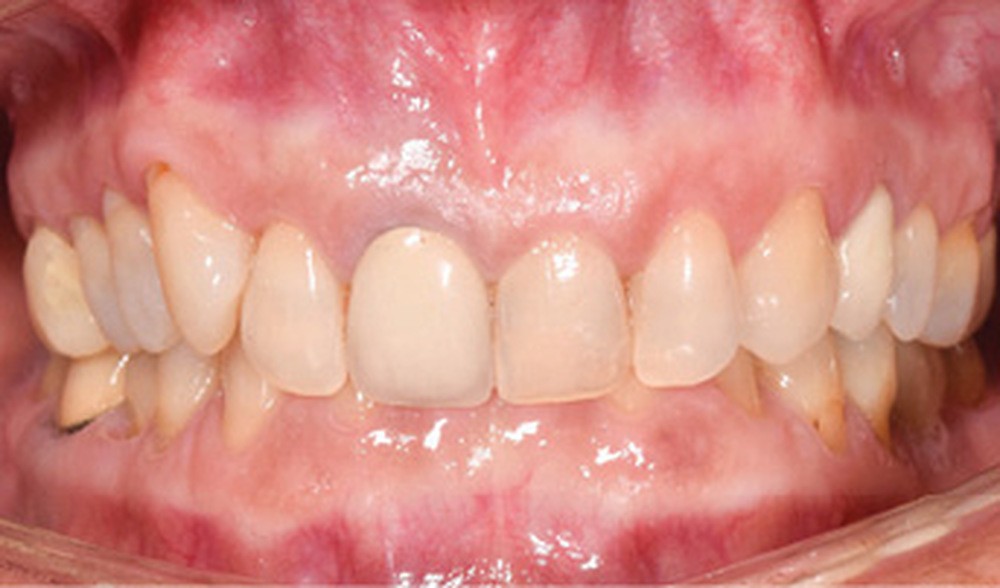

Discussion (fig. 5 à 8)

Le traitement a duré vingt-quatre mois. Les documents de fin de traitement nous montrent un sourire plus harmonieux et des rapports labiaux améliorés. De profil, la patiente a un meilleur soutien des lèvres. De plus, un léger repositionnement sagittal mandibulaire a été obtenu.

Sur la téléradiographie de profil, on note une normalisation des rapports incisifs avec un torque radiculo-palatin de l’incisive maxillaire et une vestibulo-version de l’incisive mandibulaire. La diminution de l’angle interincisif a été recherchée afin de garantir la stabilité du traitement. La superposition générale structurale révèle une rotation totale horaire qui confirme une amélioration du sens vertical.

La correction de la classe II molaire et canine a été réalisée tout en maintenant les médianes incisives centrées malgré l’implant en 36.

Il subsiste néanmoins un tip back de la 23 dû à l’effet parasite de la distalisation maxillaire.

Quant à la couronne sur la 11, il est prévu qu’elle soit refaite après éclaircissement, afin d’harmoniser sa forme et sa teinte, mais aussi la hauteur du collet avec la 21.

D’un point de vue fonctionnel, il y a eu une disparition complète de la symptomatologie douloureuse au niveau des cervicales et des ATM.